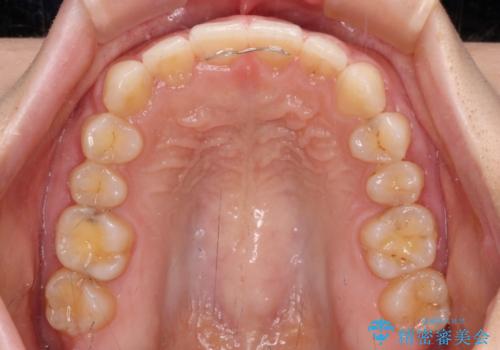

- 前歯の隙間やクロスバイトを気にして来院された患者様です。

結婚式の予定があり、可能であれば結婚式までに治療を終えたいとのことで、短期間で治療をおける可能性の高いワイヤー装置にて矯正治療を行うこととしました。

ギリギリとなりましたが、結婚式直前にワイヤー装置を外すことができました。

ワイヤー装置除去後に細かい部分を短期間のマウスピース矯正にて仕上げました。